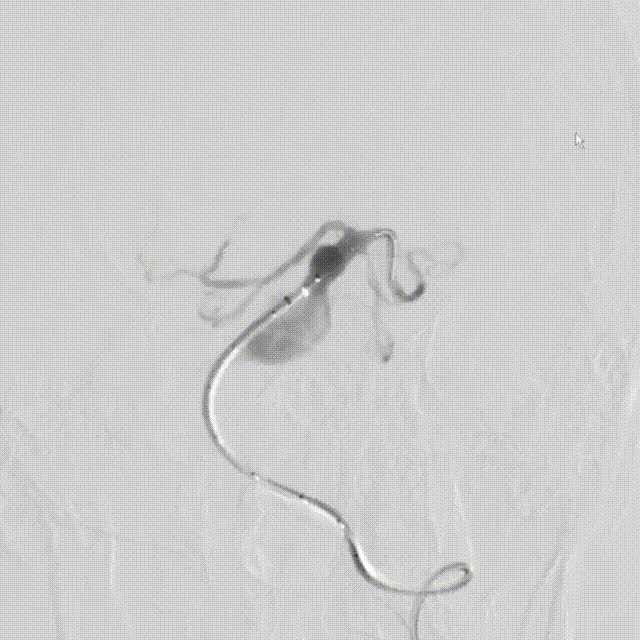

Lattice支架输送:

微导管到位。

支架输送,整体回拉定位。